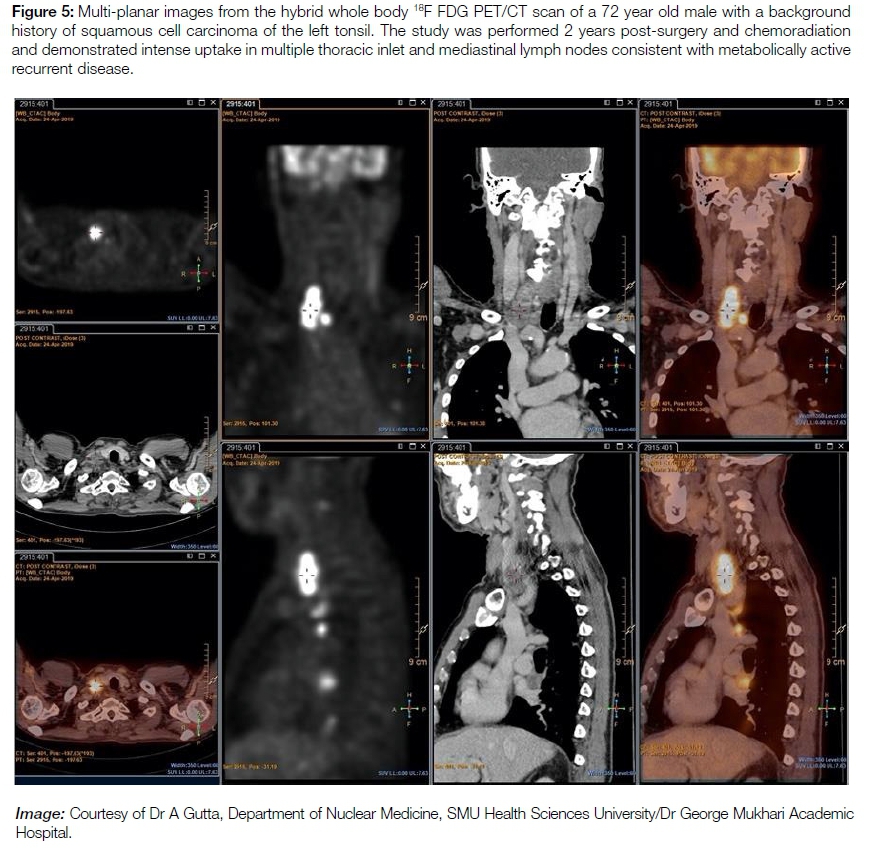

Detection of recurrence / follow-up: (see figure 5) In patients with H&N squamous cell carcinoma, early and accurate post-therapy diagnosis of recurrence offers the best opportunities for salvage treatment and prognostic prediction. Due to its ability to detect local, regional nodal and distant recurrence, FDG PET/CT is a useful modality for follow-up in these patients.16'27,28 High cost and limited availability restrict the routine use of PET/CT in this setting, but the study should be considered in patients with a high clinical suspicion in whom conventional imaging is negative or equivocal.